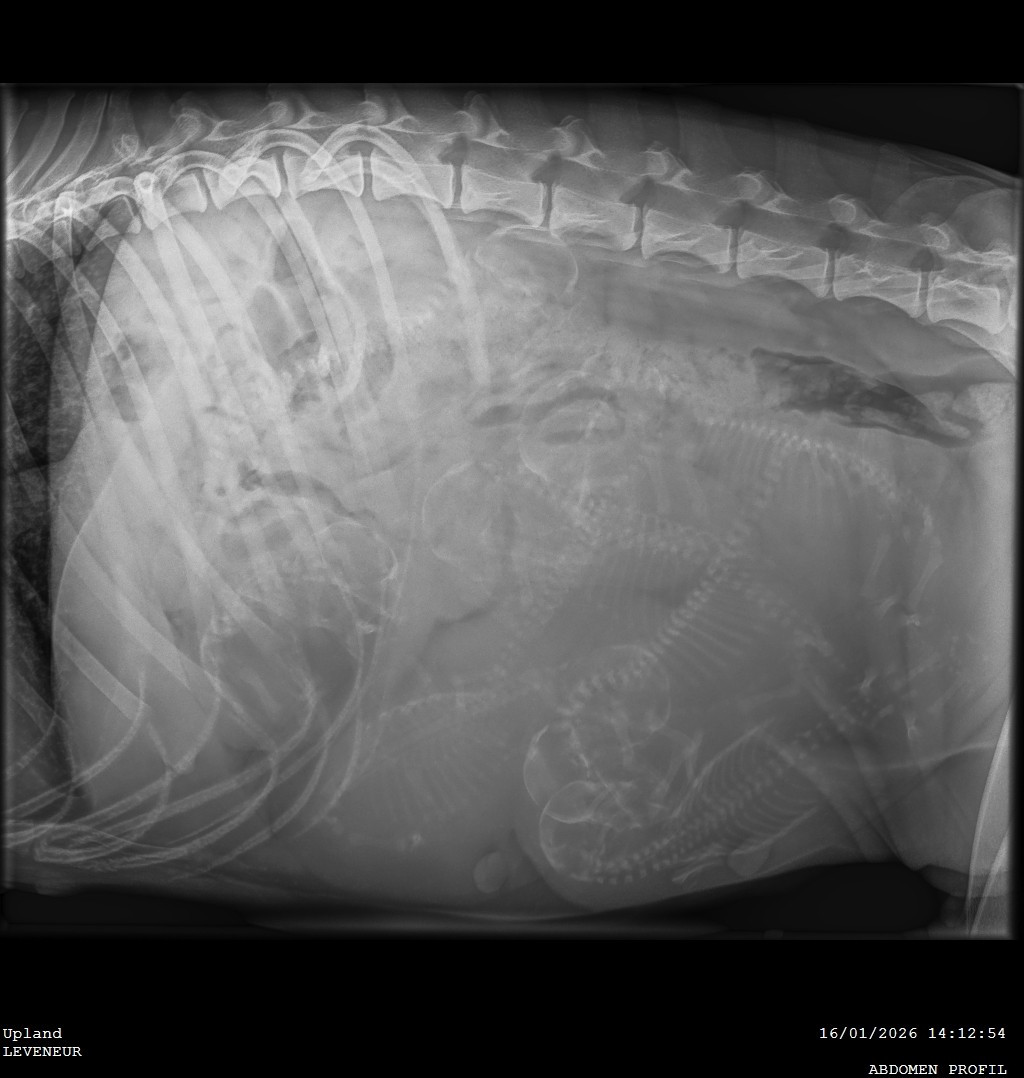

Radio de Up le 16 / 01 /2026.

Les petits diables rouges ne seront pas en retard : Ces 8, pourquoi pas 9 petits Celtes d'Artrat auront du lait...